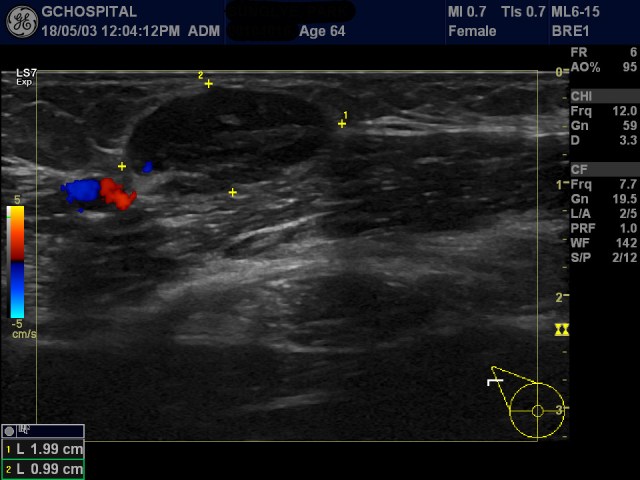

위 영상은 64세 여자환자로 우측 유방에 만져지는 병변이 있어 초음파영상을 시행한 것입니다. 경계가 분명하고 저에코의 불균질한 에코음영의 종괴가 우측 유방의 intra-lobular fat layer에 보입니다.

컬러도플러초음파영상에서는 별다른 신호가 보이지 않습니다.